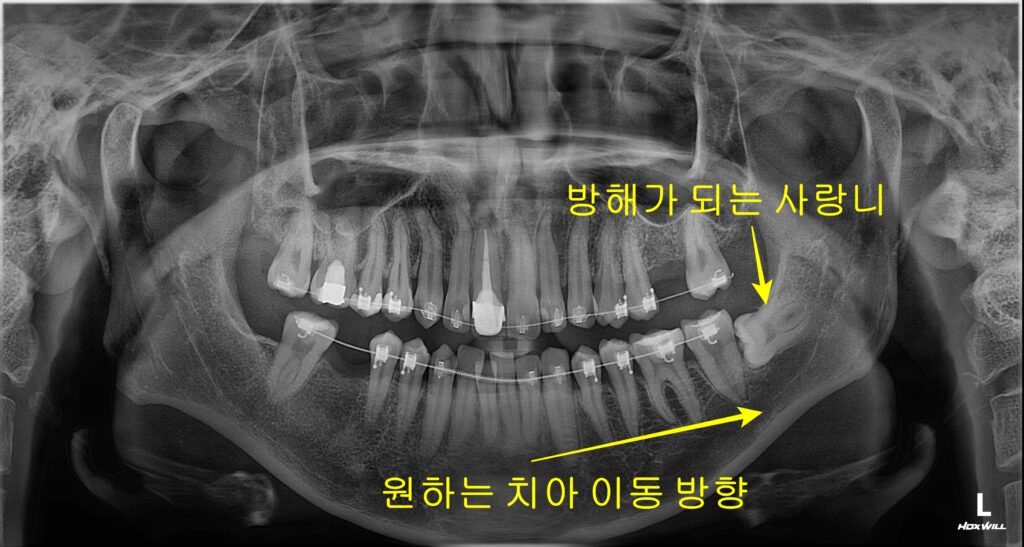

- 치아를 이동시킬 공간 확보: 덧니가 있거나 입이 튀어나온 경우를 생각해 봅시다. 치아를 가지런하게 펴거나 뒤로 당겨야 합니다. 이때 맨 끝에 있는 사랑니가 버티고 있으면 어떨까요? 치아가 뒤로 이동할 공간이 부족해집니다. 사랑니가 벽처럼 막고 있으면 교정 효과가 떨어집니다. 그래서 원활한 치아 이동을 위해 발치를 진행합니다.

STEP 1 정밀 진단 및 계획 수립 먼저 파노라마와 3D CT를 분석합니다. 하치조 신경관과 사랑니 뿌리의 거리를 파악합니다. 이번 경우는 뿌리가 신경 쪽으로 휘어 있어 주의가 필요했습니다.